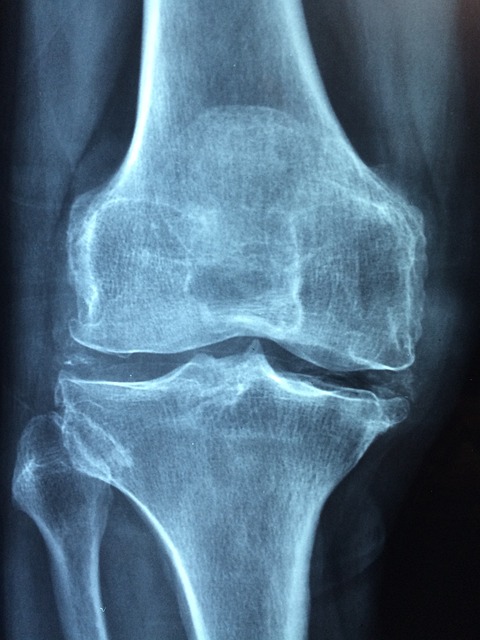

골다공증이란?

골다공증은 뼈 밀도가 낮아지고 약해져 쉽게 부러지는 상태를 말합니다. 이는 나이가 들면서 자연스럽게 발생할 수 있지만, 특히 폐경 후 여성들에게 흔히 나타나는 질환입니다.

주요 원인으로는 나이 증가, 호르몬 변화, 영양 부족, 운동 부족 등이 있습니다. 골다공증은 뼈의 강도가 약해져 골절 위험을 크게 증가시키며, 초기에는 뚜렷한 증상이 없지만 시간이 지나면서 키가 줄어들거나 허리 통증이 발생하고, 작은 충격에도 쉽게 뼈가 부러질 수 있습니다.

이 질환은 단순한 뼈 약화로 끝나지 않고 삶의 질을 크게 저하시키며, 심각한 건강 문제로 이어질 수 있습니다. 예를 들어 골절 후 회복이 어려워 일상생활에 지장을 줄 수 있고, 심한 경우 장기적인 의료 지원이 필요할 수 있습니다.